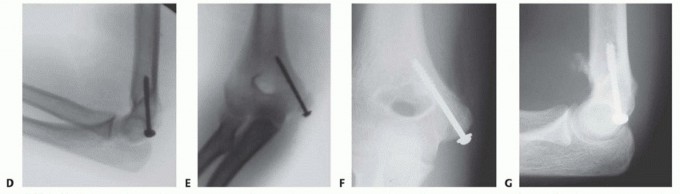

5. Provisional Fixation

Once anatomical reduction is achieved, it is provisionally stabilized using 1.6 mm or 2.0 mm Kirschner wires (K-wires) or the guide pins from a cannulated screw system. The trajectory of these pins is absolutely critical. The starting point is on the anterior-inferior aspect of the medial epicondyle. The pins are directed superiorly, laterally, and anteriorly into the distal humeral metaphysis.

Directing the pins anteriorly is paramount to avoid penetrating the olecranon fossa. A second pin is highly recommended to provide rotational stability during the subsequent drilling and tapping phases. Following pin placement, the reduction and pin trajectory are rigorously evaluated using orthogonal AP and lateral fluoroscopy. The elbow is taken through a gentle range of motion under live fluoroscopy to confirm that the hardware does not impinge on the joint and that the reduction remains stable under dynamic stress.

6. Definitive Fixation

For definitive fixation, a 4.0 mm or 4.5 mm partially threaded cannulated screw is the gold standard. The appropriate screw length is determined using a depth gauge over the primary guide pin. The lateral cortex of the humerus should ideally be engaged to maximize pull-out strength, particularly in older patients or those with osteopenic bone.

The outer cortex of the epicondyle is overdrilled to create a gliding hole, facilitating interfragmentary compression. The screw is then advanced over the guide wire. If the epicondylar fragment is comminuted or if the patient is very young with a soft, cartilaginous apophysis, a spiked ligament washer or a standard low-profile washer should be utilized to distribute the compressive forces and prevent the screw head from burying into the fragment.

Once the primary screw is seated and excellent compression is achieved, the secondary anti-rotation K-wire is typically removed, unless the fragment is highly unstable, in which case it may be exchanged for a smaller secondary screw. Final fluoroscopic images are obtained to verify anatomical reduction, appropriate hardware length, and clearance of the olecranon fossa. The ulnar nerve is inspected one final time to ensure it is free from tension or hardware impingement before the wound is closed in layers.